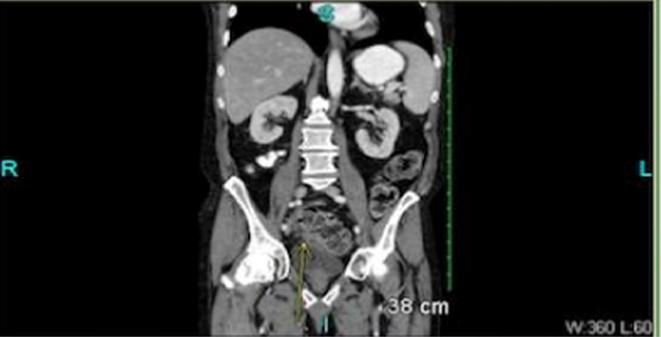

Here we report a 64-year old male with past medical history of kidney stones who was admitted for treatment of colitis which was complicated by septic shock requiring vasopressors. His course was further complicated by hyperkalemia attributed to acute kidney injury. One dose 30 gm of SPS was administered which normalized his serum potassium. The patient's course was complicated by duodenal ulcer, and colonic perforation. The initial pathology findings of the resected specimen were suggestive of inflammatory bowel disease which resulted in starting patient on mesalamine. The patient then developed fistula which was resected and sent for pathology. SPS induced colonic necrosis was made based on the pathology findings.

在此我们报告一名64岁男性,既往有肾结石病史,因治疗并发感染性休克需使用血管加压药的结肠炎而入院。他的病情因急性肾损伤所致的高钾血症而进一步复杂化。给予一剂30克SPS后,其血清钾恢复正常。患者的病情因十二指肠溃疡和结肠穿孔而复杂化。切除标本的初步病理结果提示为炎症性肠病,这导致患者开始使用美沙拉嗪。患者随后出现瘘管,对其进行了切除并送检病理。根据病理结果诊断为SPS诱导的结肠坏死。